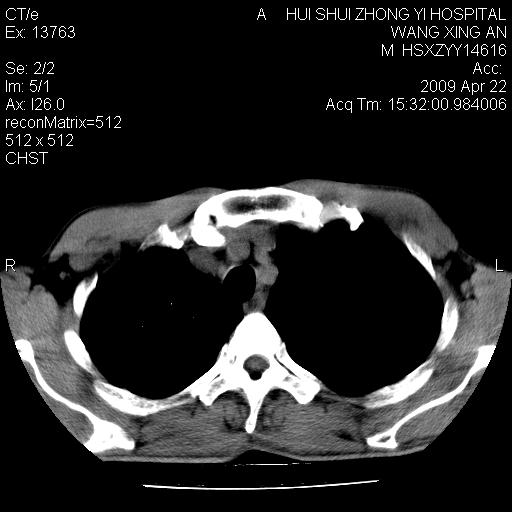

标题: CT19534:患者男、46岁咳嗽、胸痛半月。 [打印本页]

标题: CT19534:患者男、46岁咳嗽、胸痛半月。

1、右下肺中央型肺癌并右肺转移,右肺下叶不张。(肿块围绕右肺下叶支气管生长,致管腔闭塞右肺下叶不张;右肺有结节影)。

2、右侧胸腔积液。

3、右中上肺陈旧性肺结核(右肺见纤维化病灶及点状钙化)。